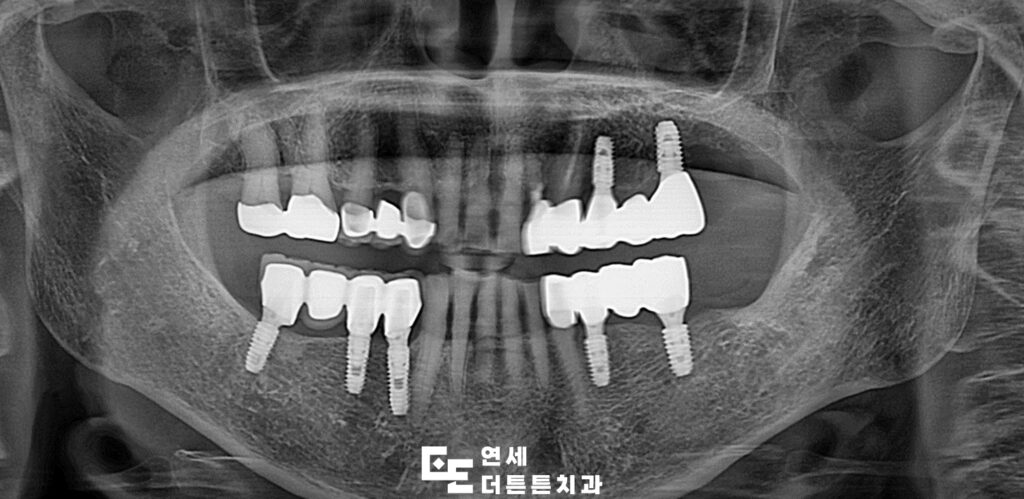

예후가 좋지 않은 치아는 발치 후 임플란트 식립, 살려쓸 수 있는 치아는 신경치료 후 크라운 수복으로 치료를 문제 없이 마무리하였습니다.

어금니는 저작 시 강한 힘이 가해지는 부위인 만큼 보다 넓은 면적과 직경을 가진 임플란트를 사용하는 경우가 많아 잇몸뼈의 양과 질이 중요한 요소로 작용하는데요. 보철물 제작 역시 어금니임플란트의 성공을 좌우하므로 교합에 직접적인 영향을 미치기 때문에 교합이 맞지 않으면 턱관절에 부담을 줄 수 있습니다. 따라서 환자의 교합 상태를 충분히 고려한 정밀한 보철물 제작이 필요합니다.